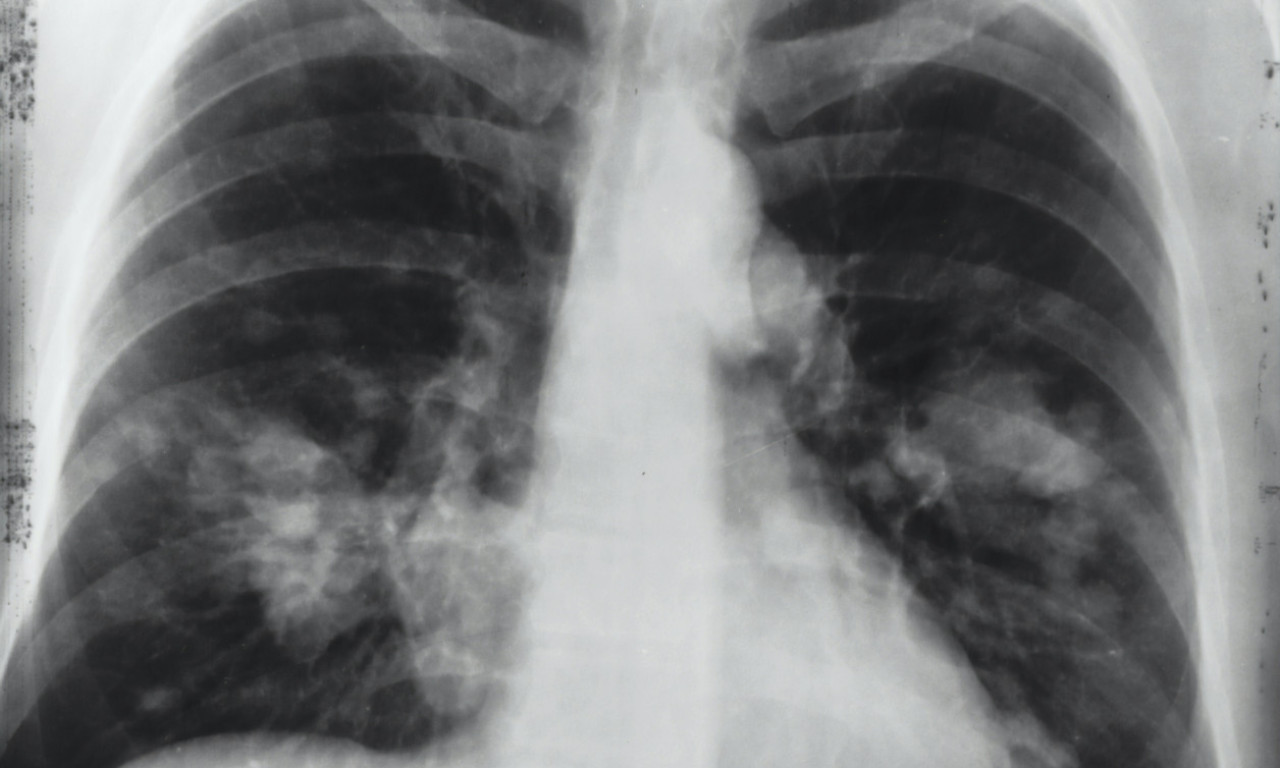

ALARMANTNI PODACI U SRBIJI! Od RAKA PLUĆA oboli 7.000 SRBA godišnje, što nas stavlja na drugo mesto u Evropi